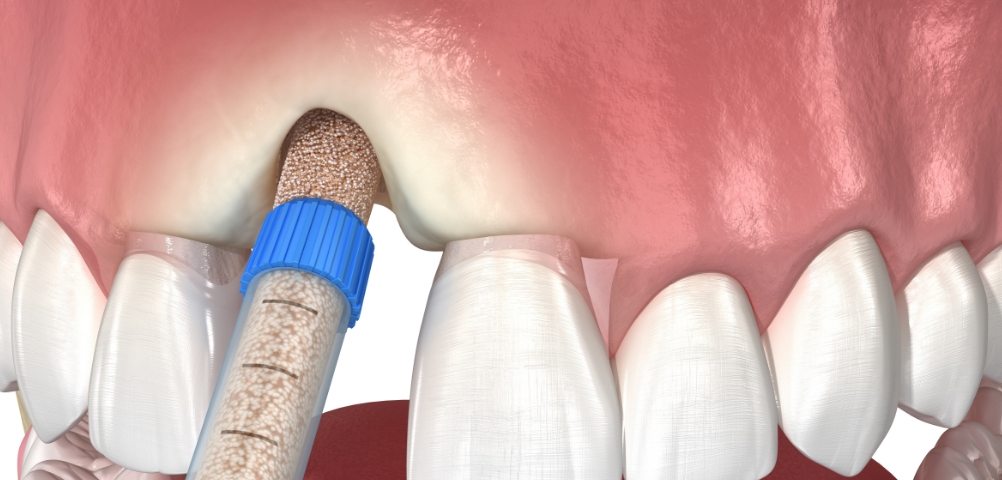

계획된 가이드에 따라 안정적으로

임플란트를 식립합니다.

임플란트를 식립하는 날, 필요한 검진·계획 후 바로 식립까지 진행되는 방식입니다.

※ 환자 개개인의 잇몸뼈·치주·전신 건강 상태에 따라 가능 여부는 달라질 수 있습니다.